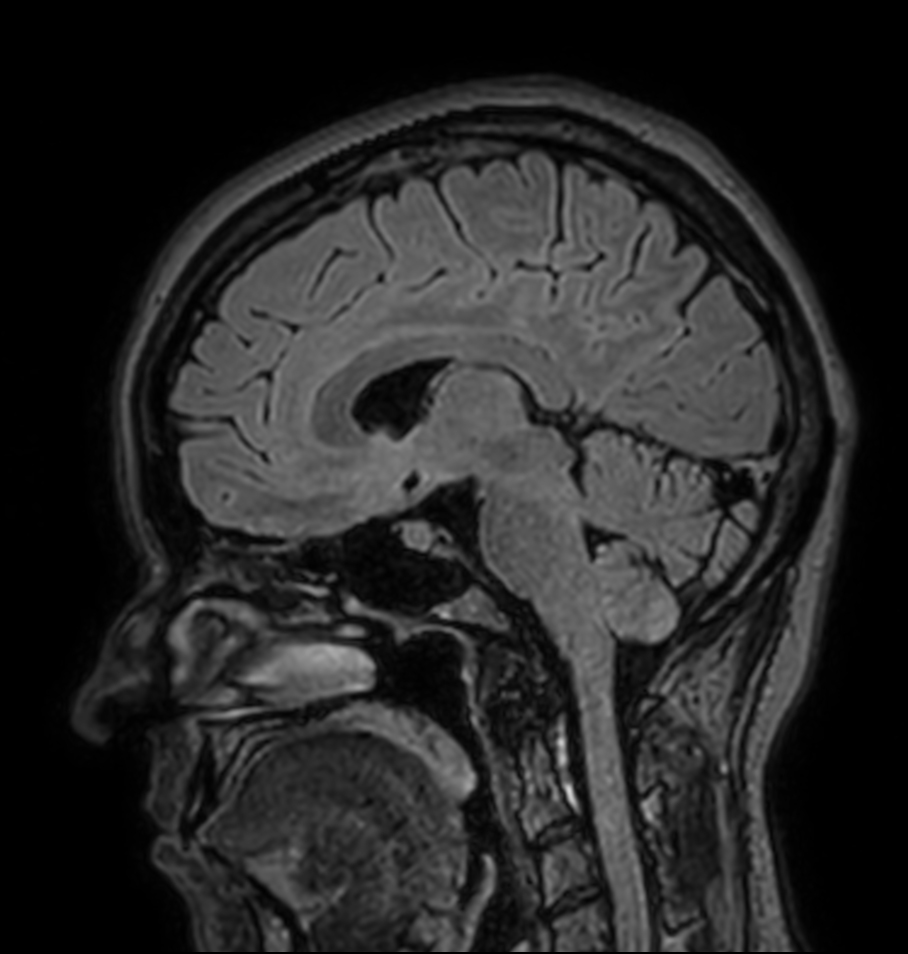

Sagittal 3D T1w TFE

Sagittal T2w TSE MultiVane XD